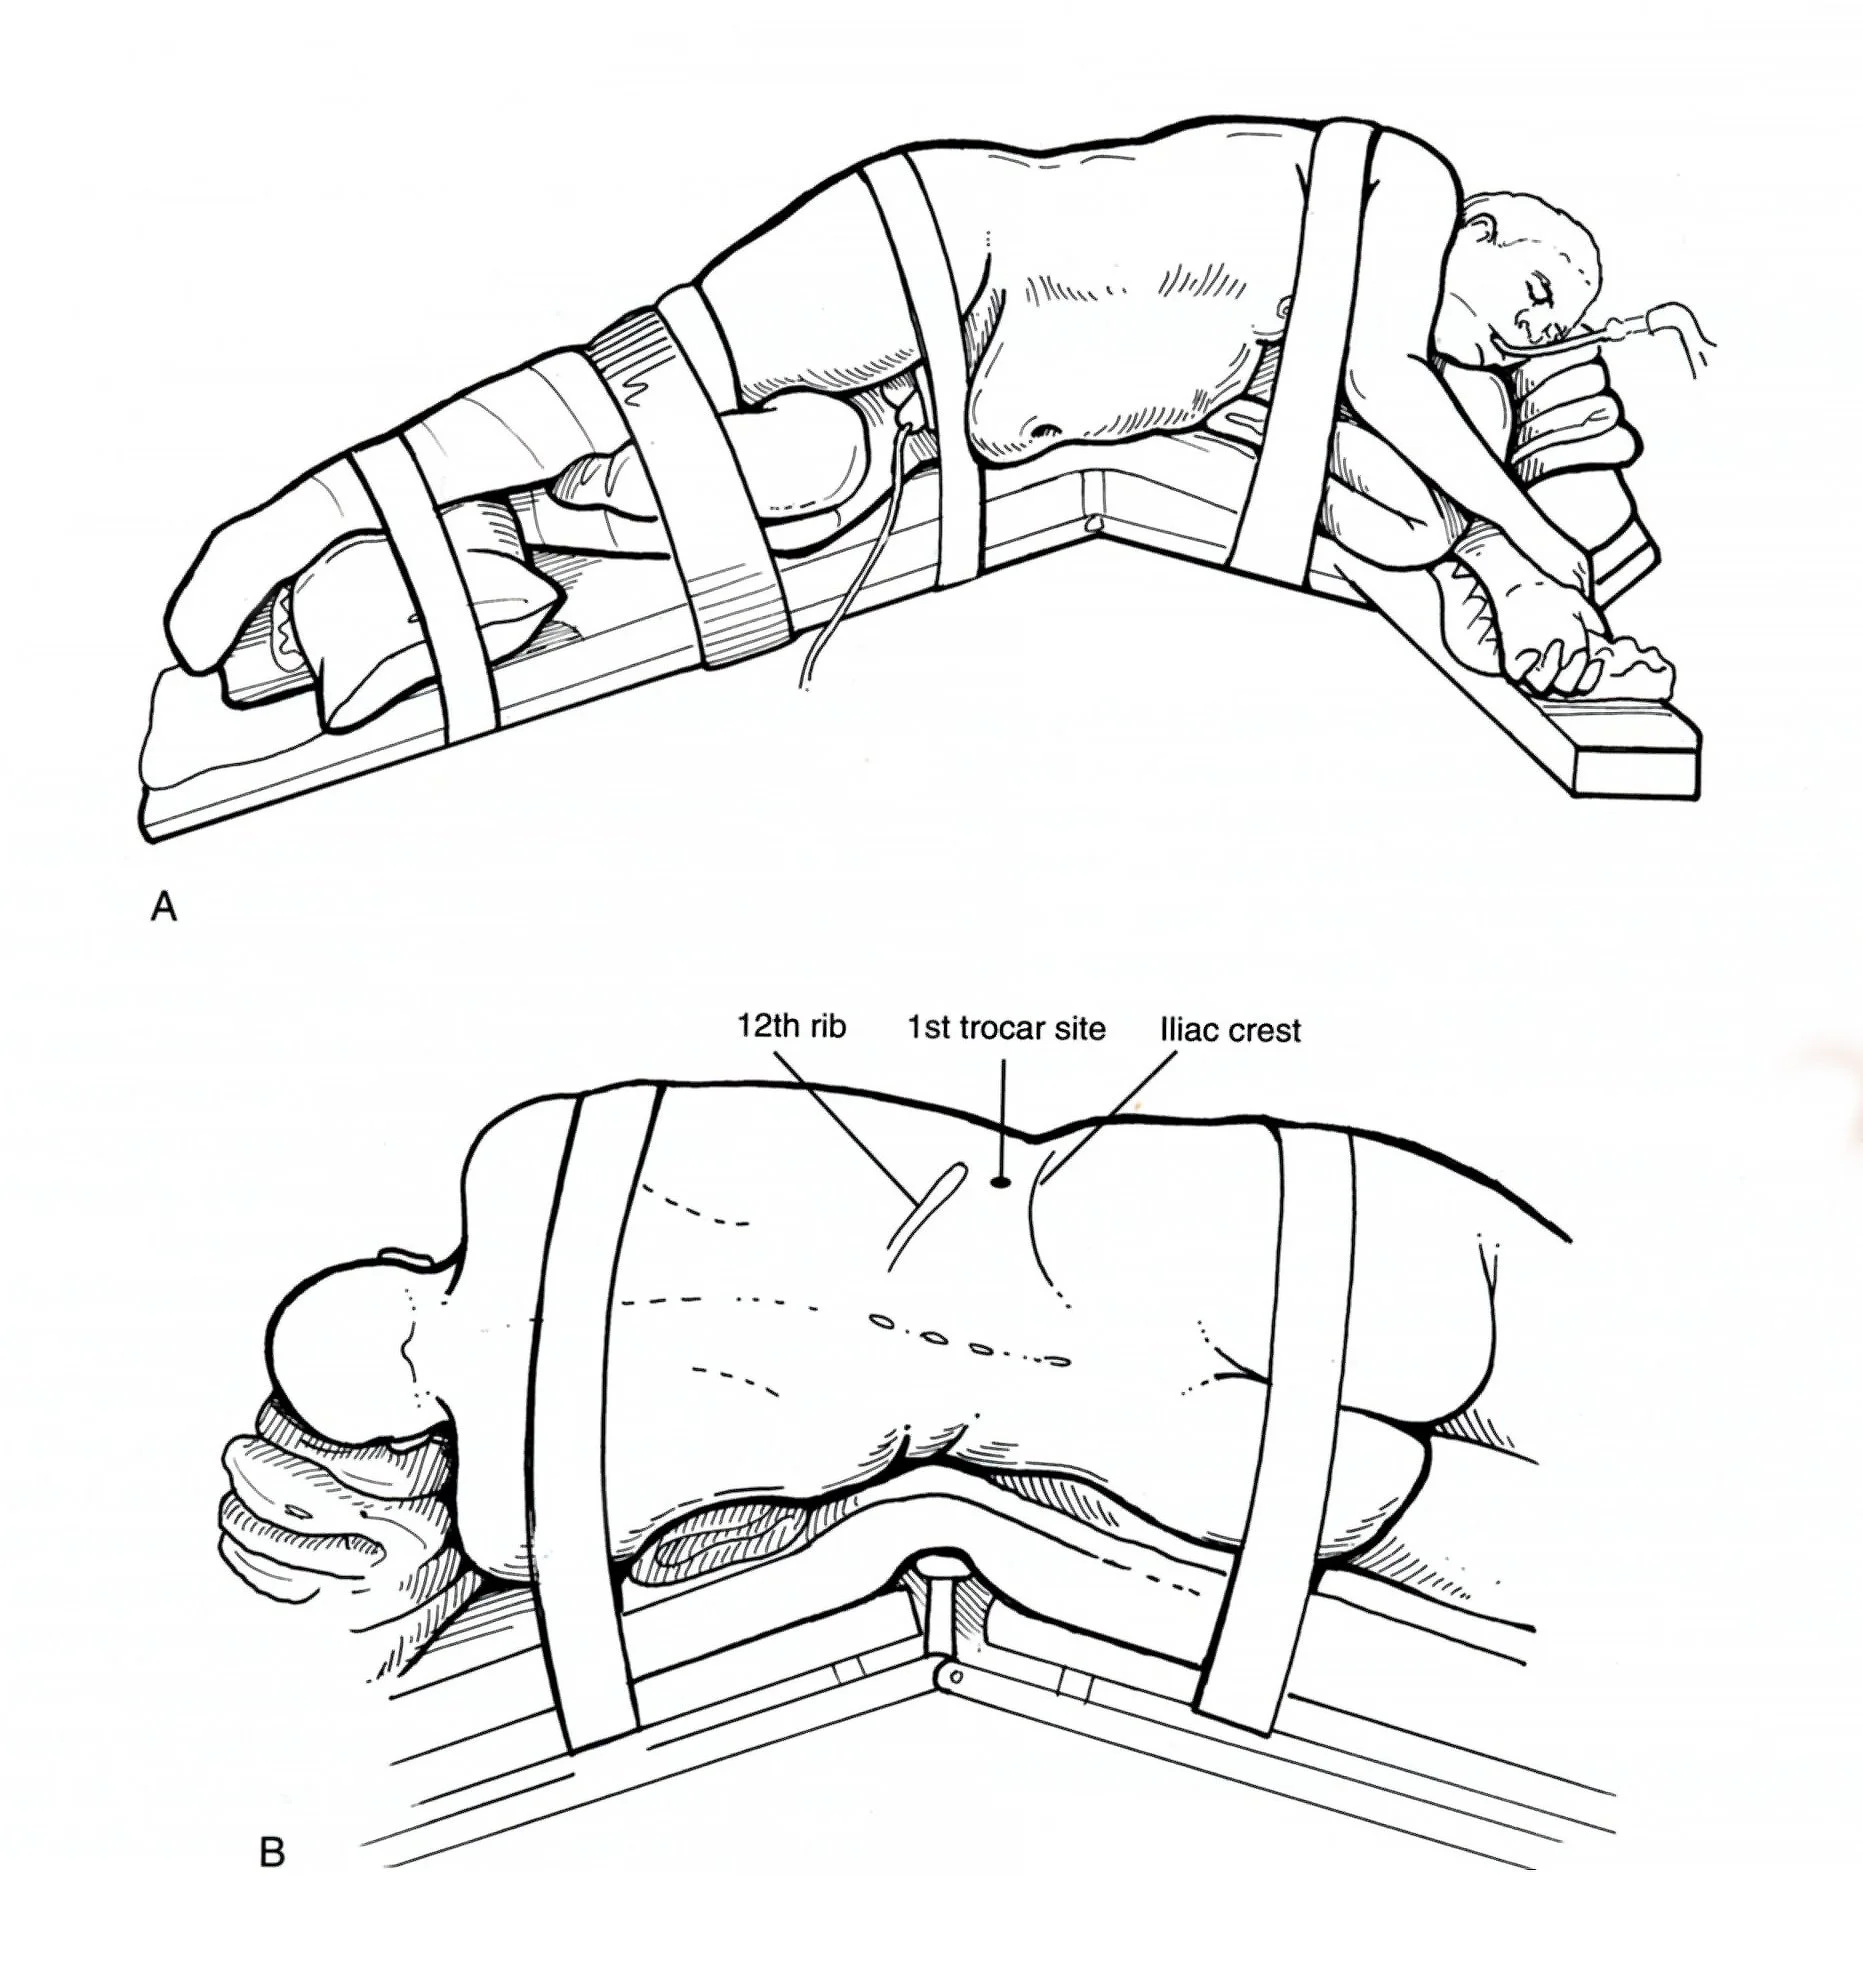

Surgical illustrations visually depict operative techniques, surgical anatomy, and complex procedures. They are created with high anatomical accuracy and serve as a visual bridge between complex surgical knowledge and learners, clinicians, or patients.